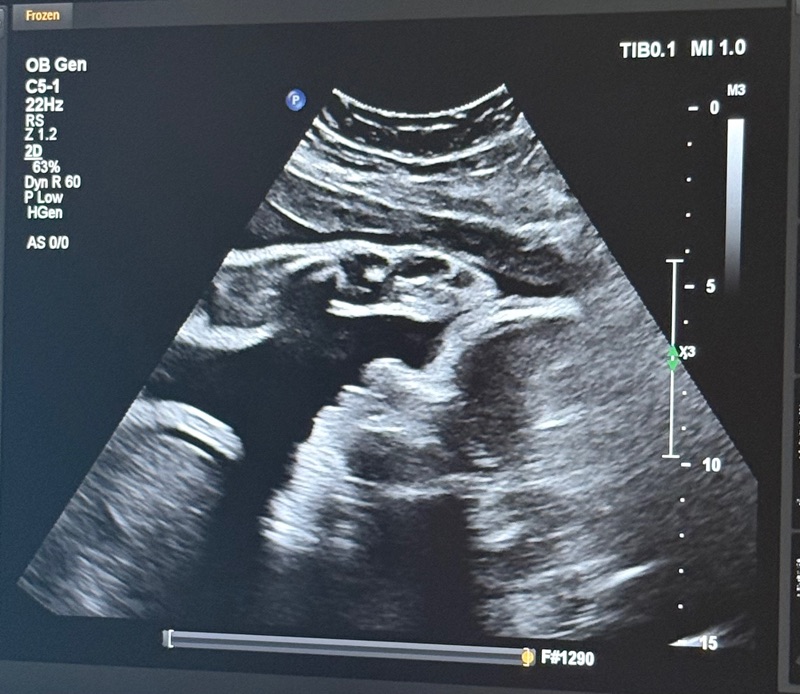

We have had a pretty good morning so far, nurses came in and gave Brandi more of the heart meds for Walker. We did just have an ultrasound to check on his heart rate, fluids, and if he is practicing breathing. According to the tech he passed all the things she wanted to see. Heart rate was still at 210. But did see him breathing. They let us take a picture of him on the monitor will attach photo. We are still waiting on talking with the OB team this morning, will more than likely talk to them after they review the ultrasound. We will keep you posted with any other updates